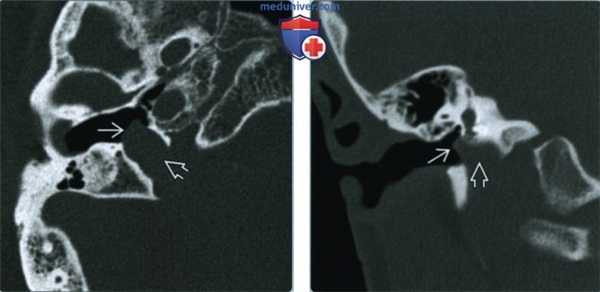

(Слева) При аксиальной КТ в коаном окне определяются луковица яремной вены и мягкотканной плотности объемное образование в нижней части правой барабанной полости, сообщающиеся через широкий дефект яремной пластинки.

(Справа) При корональной КТ в костном окне определяется дольчатое выпячивание луковицы яремной вены в правую барабанную полость. Дегисценция луковицы яремной вены -наиболее часто варечающаяся сосудистая аномалия височной кости; чаще она выявляется справа.